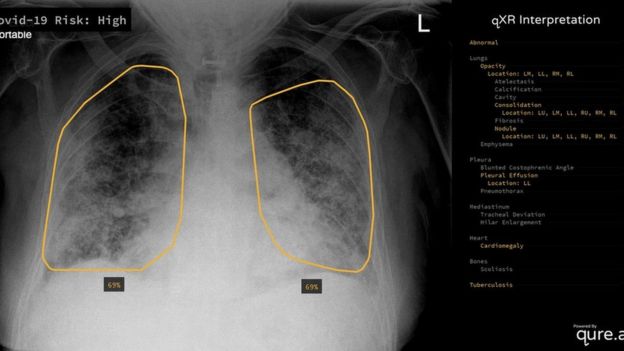

It has been running automatically on every chest X-ray the hospital has carried out for about a week, says Rizwan Malik, a radiology consultant at the hospital. This means more than 100 patients will have had X-rays analysed by the system to date, he estimates. In this case, the algorithm is designed to look for possible signs of Covid-19, such as patterns of opacity in the lungs.

“It basically gives clinicians another tool to help them make decisions – for example, which patients they’ll admit, which they’ll send home,” says Dr Malik, who notes that patient data is processed entirely within the hospital’s own network. The software itself was developed by Mumbai-based Qure.ai.

Dr Malik adds that he has provided consultancy services to Qure.ai in the past but stresses that the system went through standard checks and procurement processes before being rolled out at his hospital.